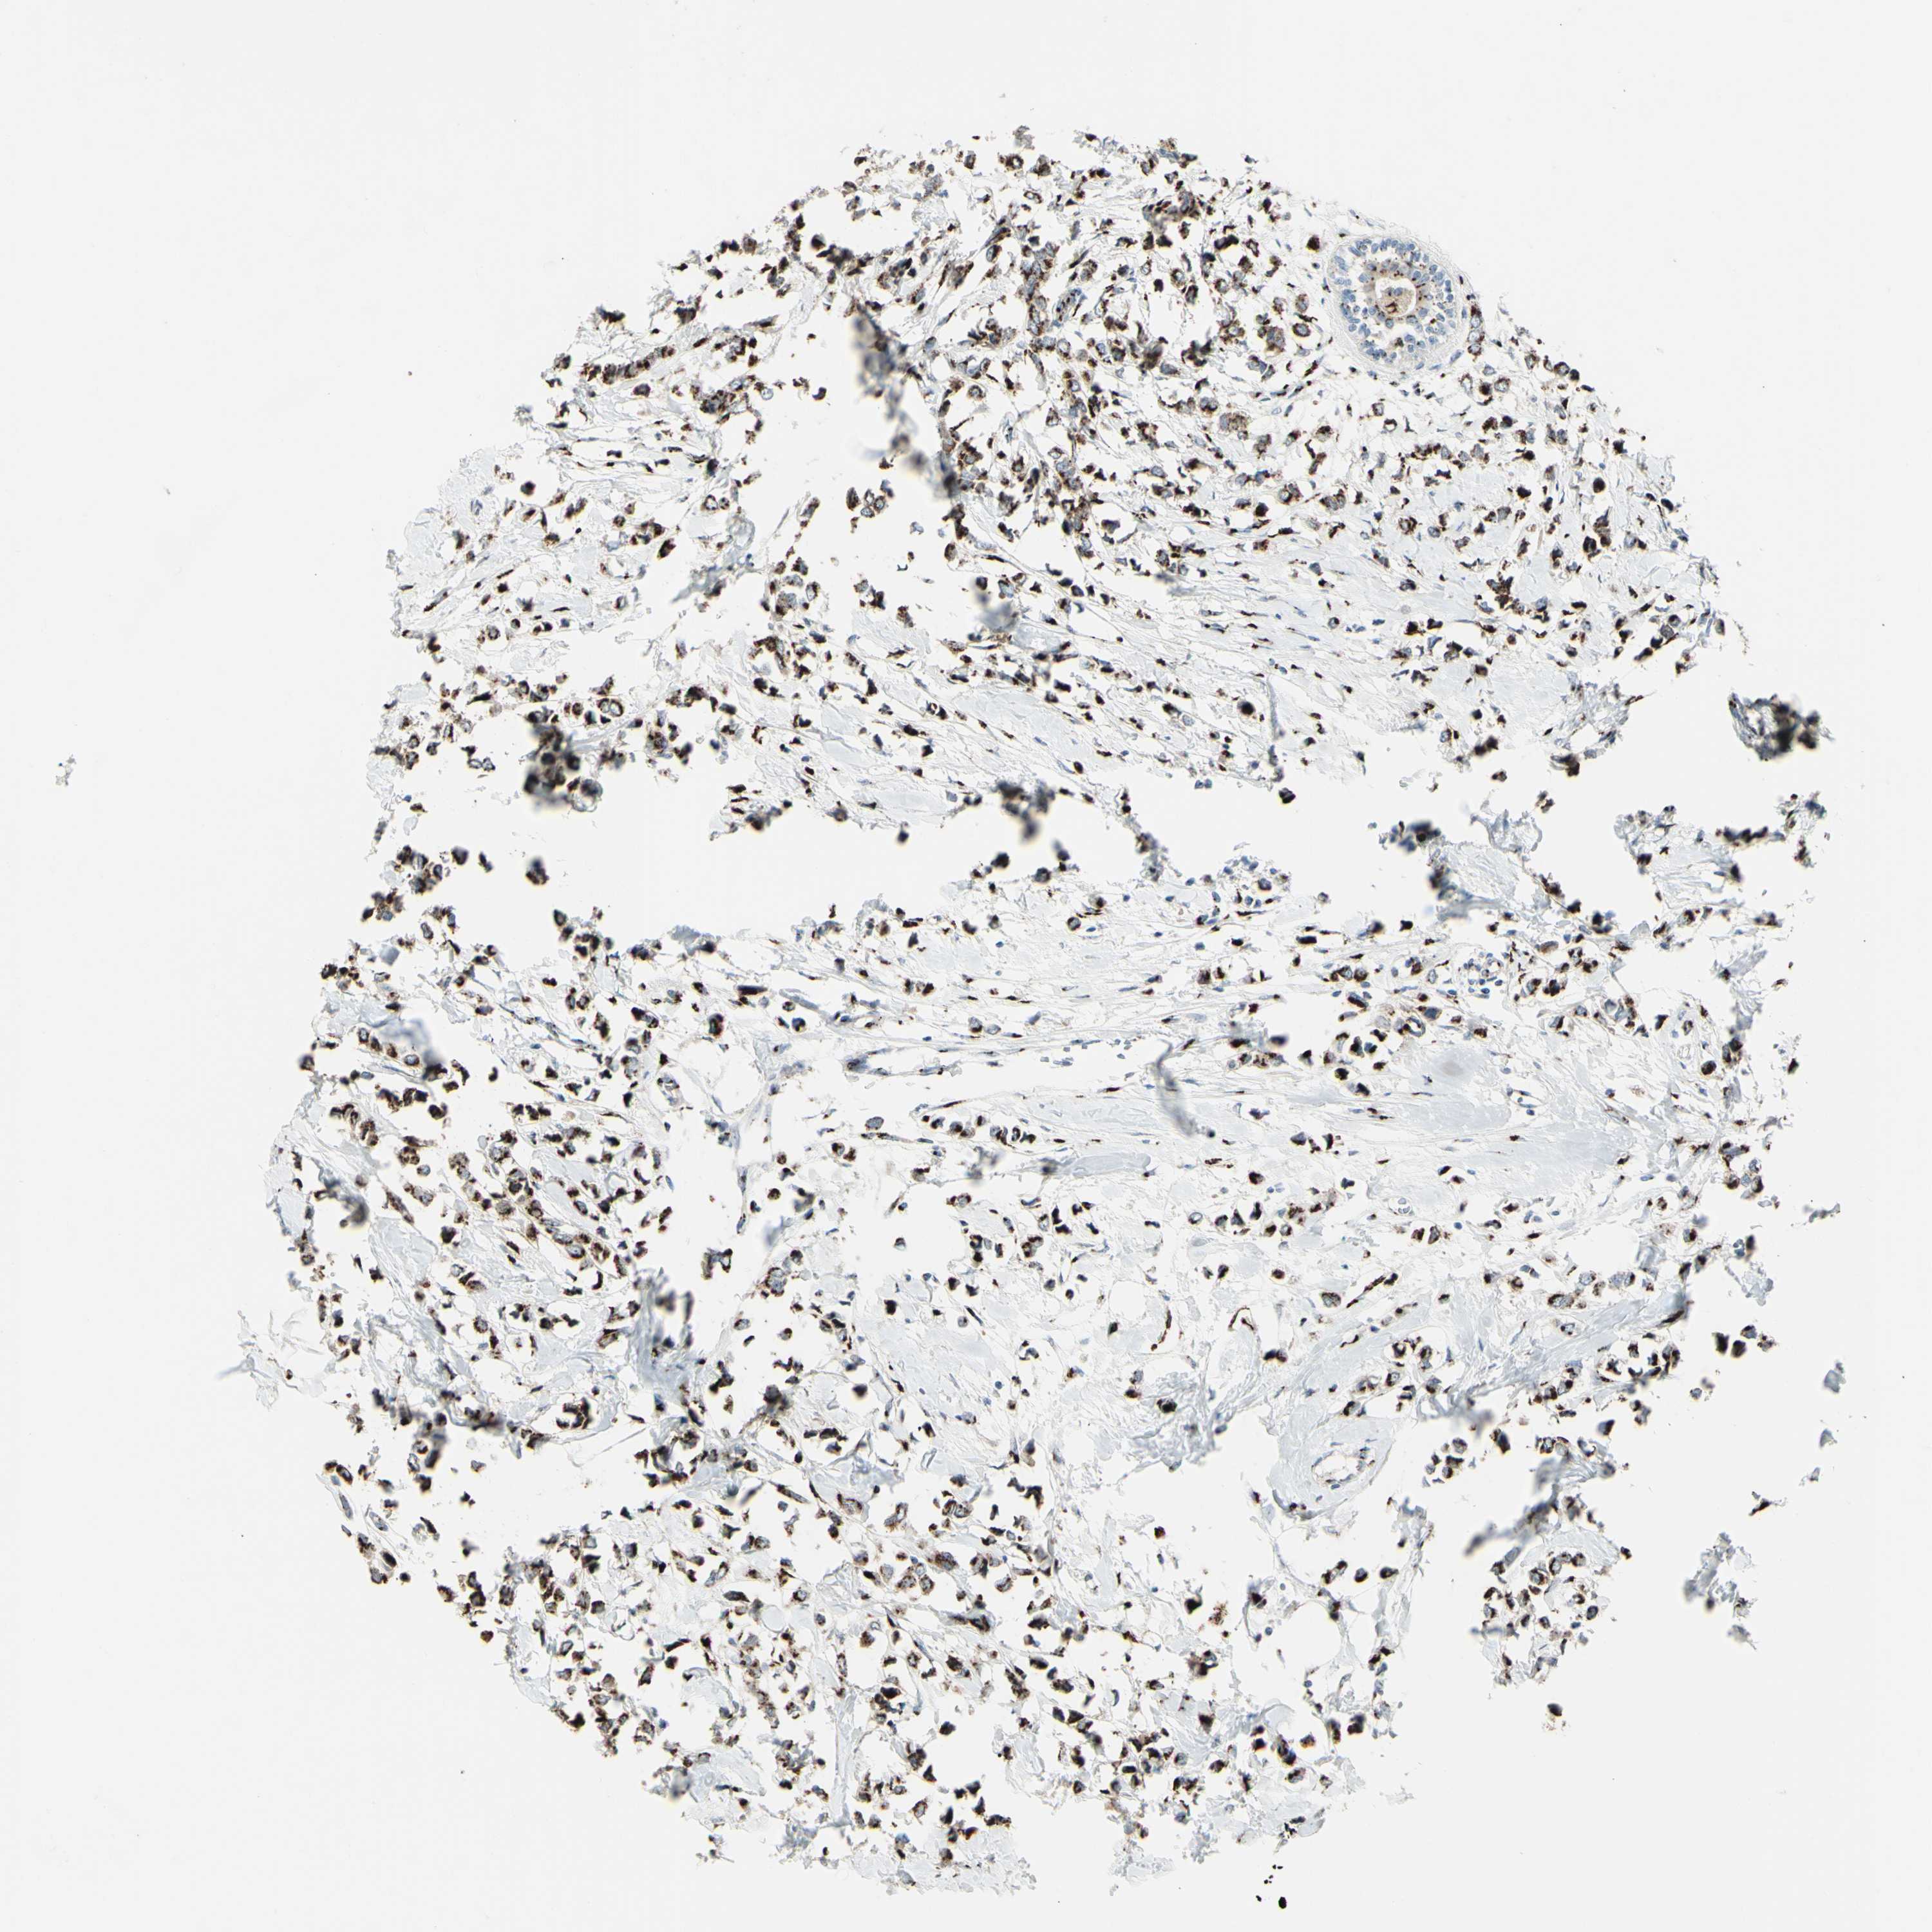

BRCA TCGA BRCA VALIDATION PROTEIN EXPRESSION

ANTIBODIES

AND

VALIDATION